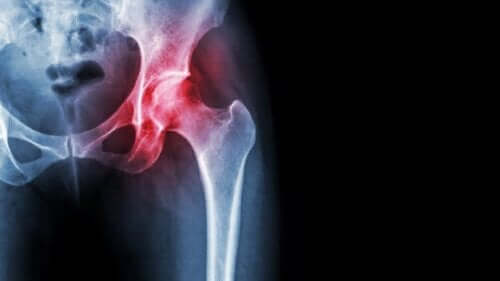

Femur Başı Avasküler Nekrozu

Avasküler nekroz, diğer tüm nekrozlar gibi, dokulara kan gitmemesinden kaynaklanır. Bu spesifik durumda kemikleri etkiler ve bu da oldukça ciddi sonuçlara yol açar.